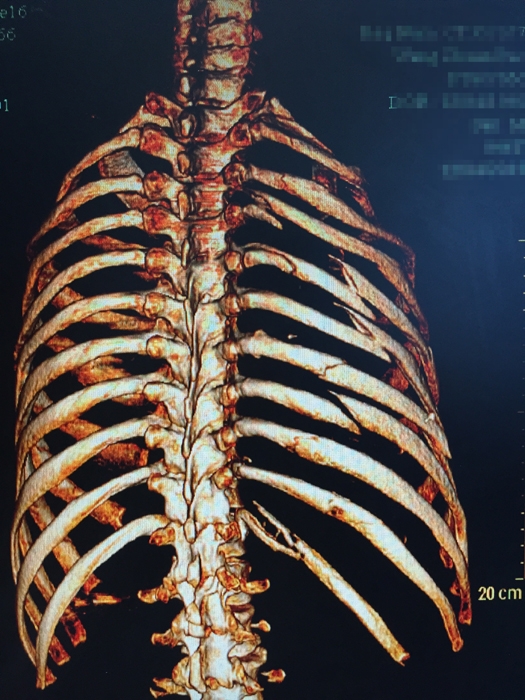

??? 說起張成的經(jīng)歷,讓人唏噓不已。2015年12月4日,46歲的張成不慎從四層高樓墜落,當場不省人事。家人立即將張成送入當?shù)蒯t(yī)院搶救,經(jīng)檢查發(fā)現(xiàn)張成血氣胸,創(chuàng)傷性濕肺,全身多處骨折,光肋骨就有11根骨折,右側股骨骨折,右側肱骨下段粉碎性骨折,最嚴重的是還有脾破裂,骨盆骨折和胸椎骨折。因傷勢嚴重,當?shù)蒯t(yī)院建議家屬將張成轉到上一級醫(yī)院。

患者入院時的X影像